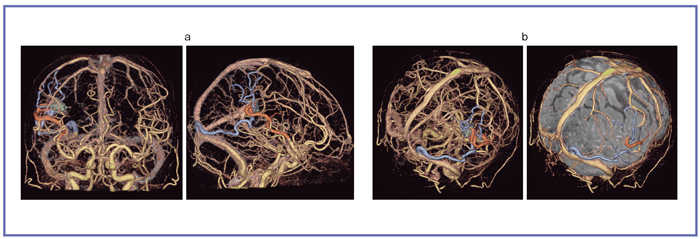

Neurosurgery10 脳動静脈奇形治療のこれまでとこれから 新到着 新NS 10】脳動静脈奇形治療のこれまでとこれから NOWの詳細情報

新到着 新NS 10】脳動静脈奇形治療のこれまでとこれから NOW。脳神経外科 専門治療 脳動静脈奇形|東京慈恵会医科大学附属柏病院。脳・脊髄動静脈奇形と頭蓋内・脊髄硬膜動静脈瘻。2017年発行の第1版です。【JMECC受講テキスト】内科救急診療指針2022【裁断済み】。脳神経領域:320列面検出器CTの最新画像がもたらす新たな展開。よろしくお願い致します。